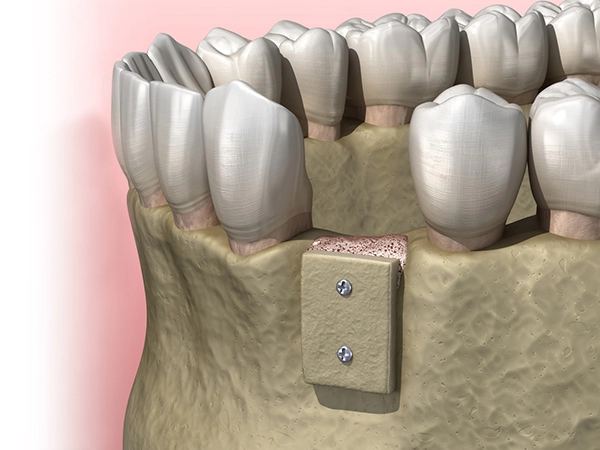

Операция проводится с помощью подсадки костного материала и закрепления его с помощью мембраны, она является одним из наиболее эффективных методов костной пластики. Используется для восстановления объема или увеличения и высоты костной ткани при истончении кости в области альвеолярного гребня на верхней или нижней челюсти. Операция проводится с применением местной анестезии и может занимать до полутора часов. Пациенты, которые страдают от вертикальной резорбции после потери зубов, нуждаются в наращивании костной ткани в пострадавшей области для установки имплантов и последующего протезирования.

Операция проводится с помощью подсадки костного материала и закрепления его с помощью мембраны, она является одним из наиболее эффективных методов костной пластики. Используется для восстановления объема или увеличения и высоты костной ткани при истончении кости в области альвеолярного гребня на верхней или нижней челюсти. Операция проводится с применением местной анестезии и может занимать до полутора часов. Пациенты, которые страдают от вертикальной резорбции после потери зубов, нуждаются в наращивании костной ткани в пострадавшей области для установки имплантов и последующего протезирования.

Подсадка костной ткани челюсти при атрофии и резорбции: восстановление необходимого объема костной ткани для постановки имплантатов

Подсадка костной ткани челюсти при атрофии и резорбции: восстановление необходимого объема костной ткани для постановки имплантатов

Подсадка костных блоков – это операция по изъятию собственного костного материала и подсадка его в дефицитные зоны на нижнюю или верхнюю челюсть. Применяется для восстановления объема костной ткани при установке имплантов.

Подсадка костных блоков – это операция по изъятию собственного костного материала и подсадка его в дефицитные зоны на нижнюю или верхнюю челюсть. Применяется для восстановления объема костной ткани при установке имплантов.